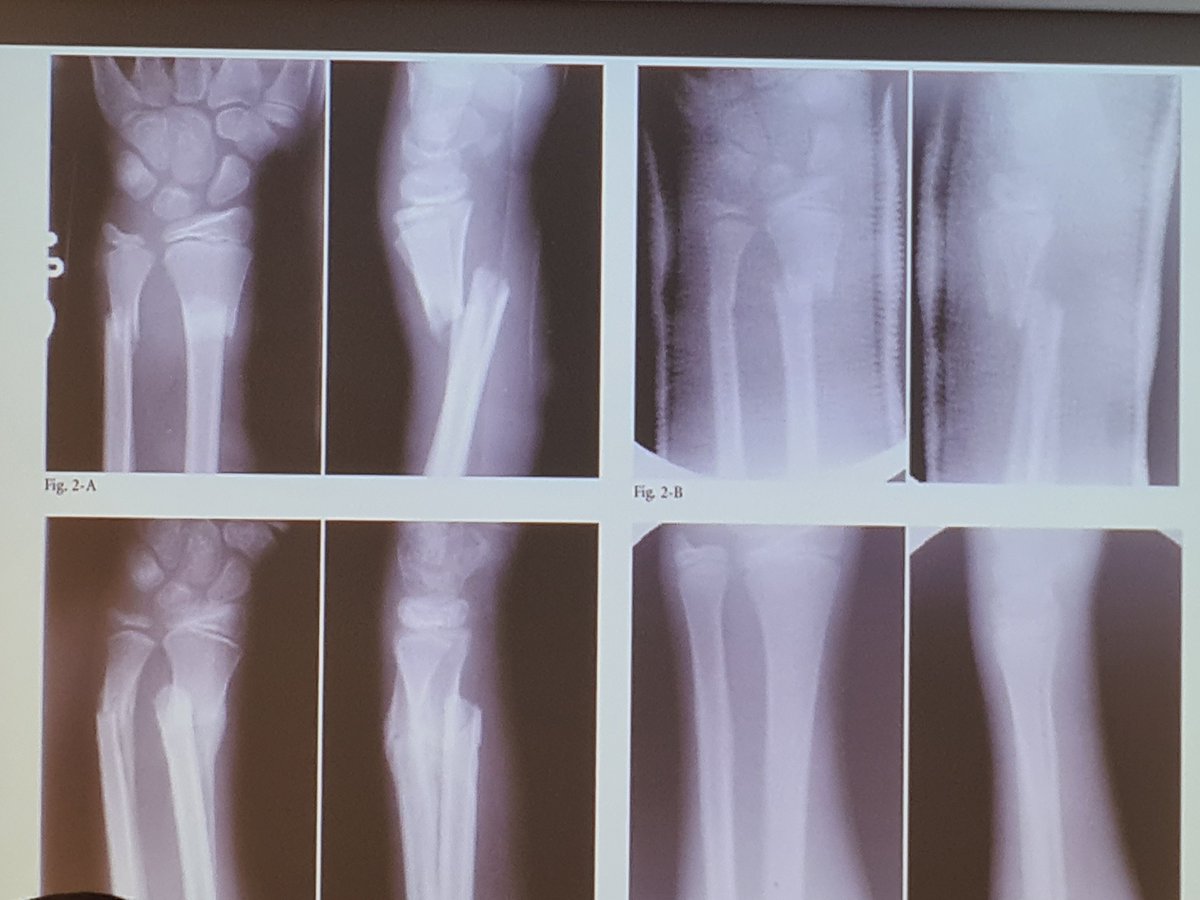

Operations carry risk - 7% re-operation and 17% total for K-wiring in distal radial fractures.

Growing evidence base for less intervention and more conservative management with good outcomes. Also saves a lot of theatre time too. Look at this 👇 Image Parents would typically opt for conservative management if outcomes are thought to be good too.